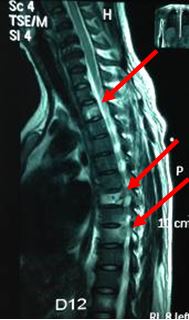

Chụp cộng hưởng từ cột sống: Tổn thương phá hủy xương D2, D7, D9 và tổn thương cung sau xương sườn tương ứng

Hình 3: Hình ảnh cộng hưởng từ cột sống: Tổn thương phá hủy xương D2, D7, D9, tổn thương cung sau xương sườn tương ứng

- Chụp cộng hưởng từ cột sống: Xẹp thân đốt sống D7, tổn thương thân đốt sông D2 và D9

Hình 7: Hình ảnh cộng hưởng từ cột sống sau điều trị 3 chu kỳ hóa chất: Tổn thương xẹp thân đốt sống D7, tổn thương thân đốt sống D2,D9